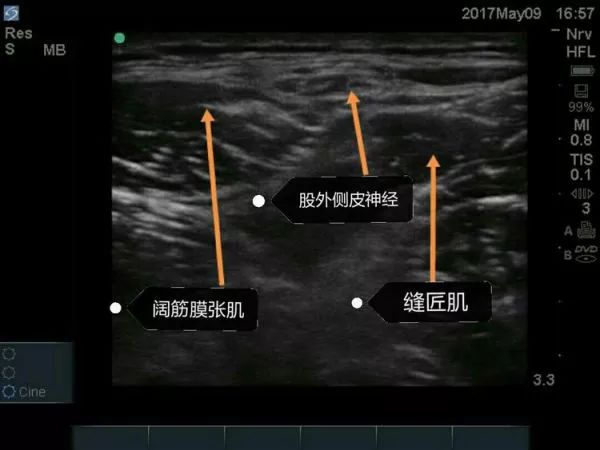

超声下股外侧皮神经阻滞要点

①适应证: 髋部手术的术后镇痛,感觉异常性股痛,大腿近端外侧肌肉活检。

②探头的位置: 横向放置,紧贴髂前上棘的下方,缝匠肌SaM的外侧缘。

③目标: 局麻药在阔筋膜张肌TFL和缝匠肌之间扩展。

④局麻药: 5-10ml。

超声引导下股外侧皮神经阻滞技术为骨科髋关节手术切口提供理想术后镇痛效果。

超声引导下局麻药在股外侧皮神经周围扩散